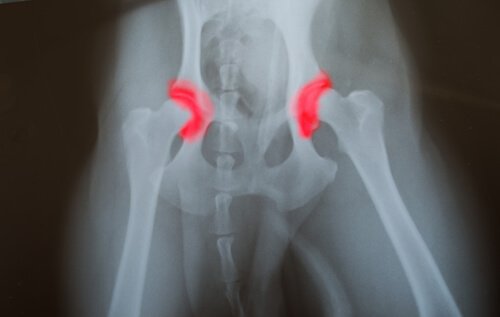

Hüft- oder Ellenbogendysplasie ist eine vererbte Krankheit, die von Generation zu Generation weitergegeben wird. Die Knochen eines Gelenks, entweder der Hüfte oder des Ellenbogens, sind dabei nicht richtig platziert oder ausgerichtet.

So kommt es dazu, dass sie aneinander reiben und schädliche Bewegungen zur Folge haben. Das hingegen führt zu einer übermäßigen Abnutzung und fehlerhaften Funktion des Gelenks. Das Problem hierbei ist, dass die Krankheit still voranschreitet.